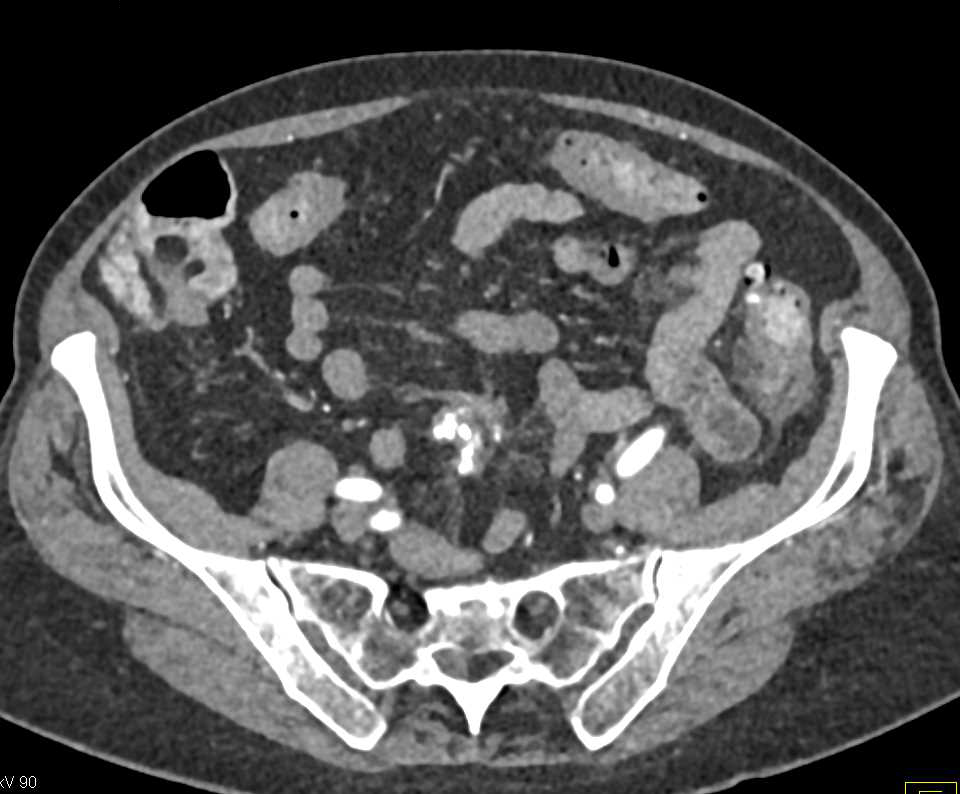

Melanoma with Distal Small Bowel Intussusceptions